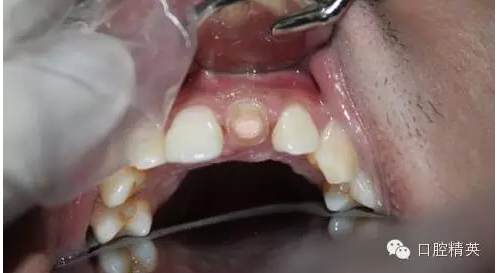

一年輕小伙,在打籃球中,被隊友打斷門牙,來本診所時已經(jīng)露髓,局麻拔髓后,行RCT。后因經(jīng)濟(jì)關(guān)系,擬鈷鉻樁加鈷鉻烤瓷冠修復(fù),備牙后才留照片:

1:牙根,備牙后,

2:唇側(cè)觀,